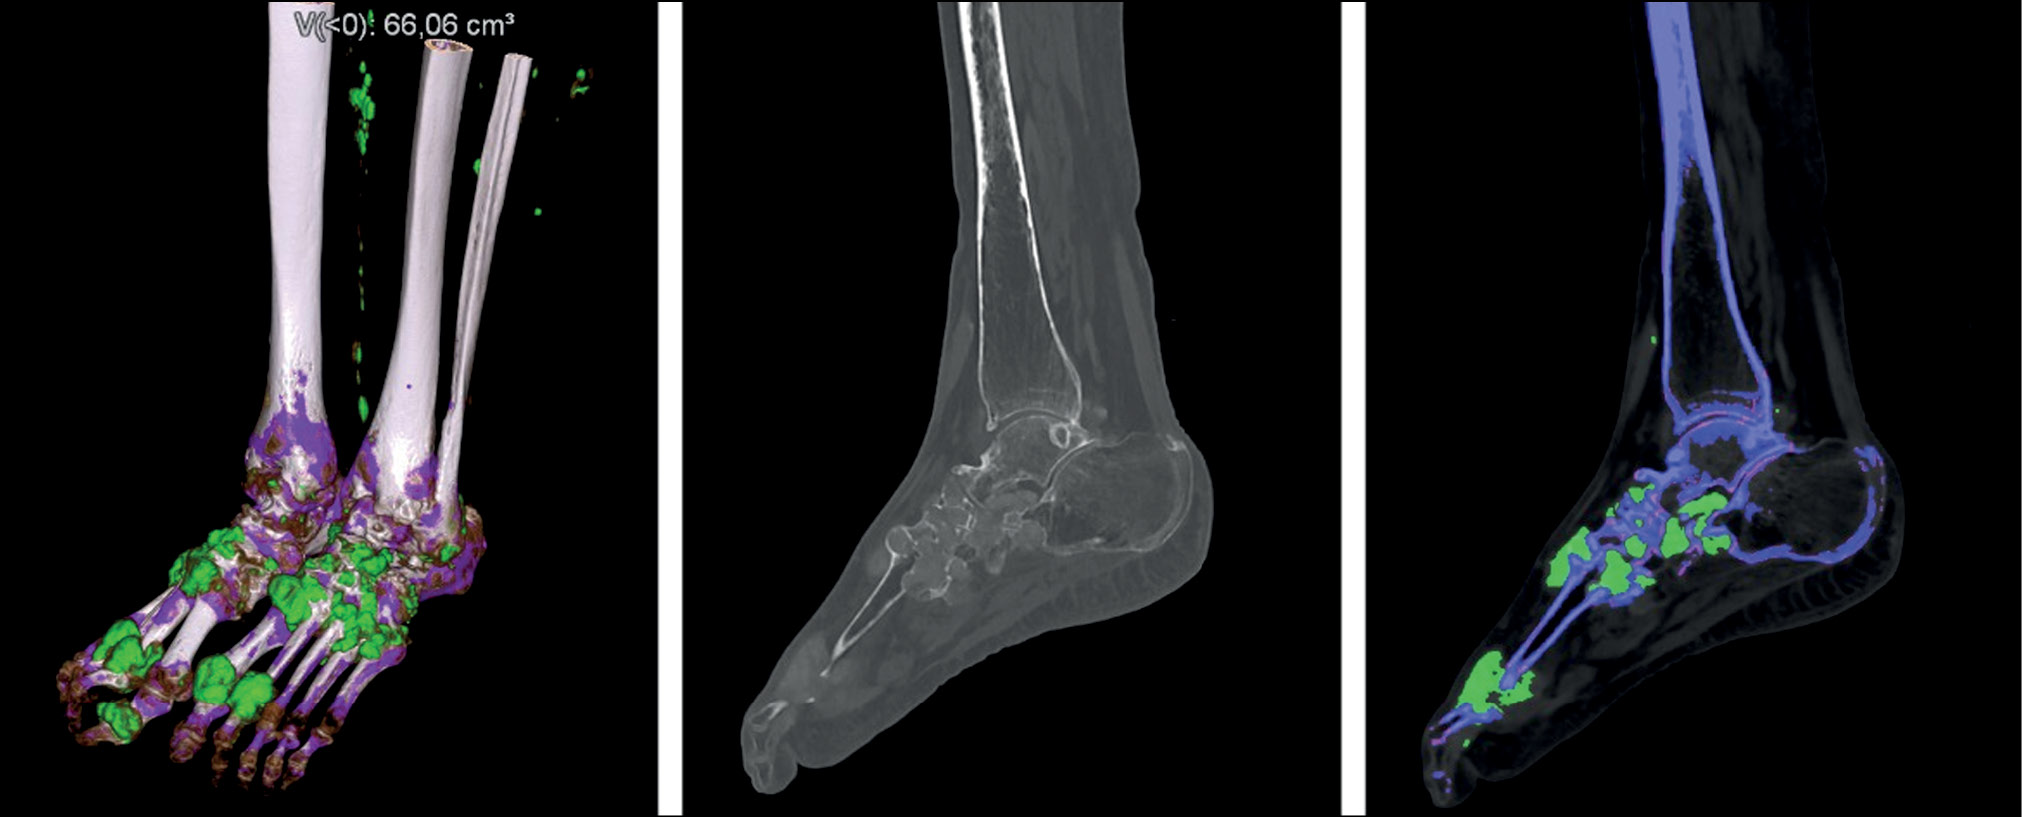

DECT has several configurations: with two perpendicular sources and detectors, with a single source-detector system with quick voltage switching, or with a single X-ray source and a multilayer sandwich detector [26]. Data are processed using three- or two-material decomposition analysis. Two-material decomposition analysis in the diagnosis of gout is performed by uric acid and calcium. Soft tissues are the “reference point” for the algorithm to make judgment concerning the presence of calcium or monosodium urate in the area under study. Thus, a material density (MD) map can be created, on which each component is color coded. In the Siemens DECT systems, cortical bones, cancellous bones, and monosodium urate crystals are coded blue, pink, and green, respectively. Color scales used by other manufacturers’ processing algorithms may differ.

In addition to the qualitative assessment, a quantitative assessment of the chemical of interest is possible. The dual-energy gout software automatically determines the total volume of monosodium urate deposits in the field of view (FOV) [23]. Artifacts are included in the total volume; therefore, understanding their types and potential location is critical. Green areas corresponding to artifacts can be removed using the cropping tool. After this, the total volume of monosodium urate deposits will be automatically recalculated.

Three-dimensional reconstruction (volume-rendering technique image) with color coding is possible, as are other reconstruction algorithms employed in research (Fig. 2).

Fig. 2. Three-dimensional reconstruction, blended and color-coded image (right ankle joint and small foot joints): blue, pink, and green represent cortical bone, cancellous bone, and monosodium urate crystals, respectively (dual-energy computed tomography findings of the Medical Research and Education Center of the Lomonosov Moscow State University).